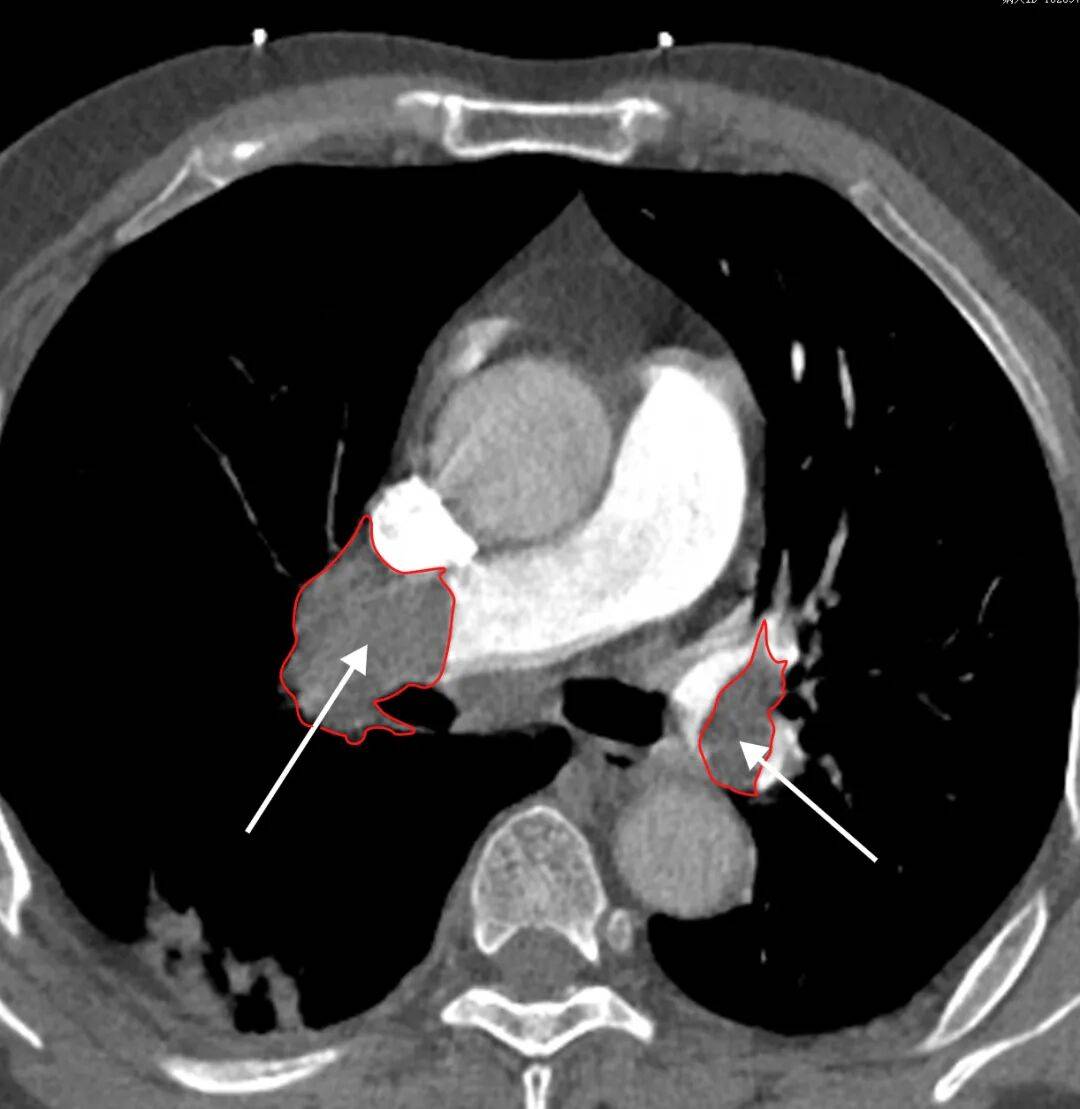

检查原理:通过肘静脉注射含碘造影剂,再用CT快速扫描肺部血管,让堵塞血管的血栓“显形”——影像上会看到肺动脉内有“充盈缺损”(就像水管里卡了一块石头,水流无法通过)。该检查速度快、准确率高,能清晰显示直径1-2毫米的小血栓,还能同时排查肺部感染、肿瘤等其他疾病,是目前各级医院诊断肺动脉栓塞的选择。

(上图CTPA为肺栓塞,可见黑色充盈缺损为肺动脉栓子堵塞了肺动脉血管通路(箭头处))